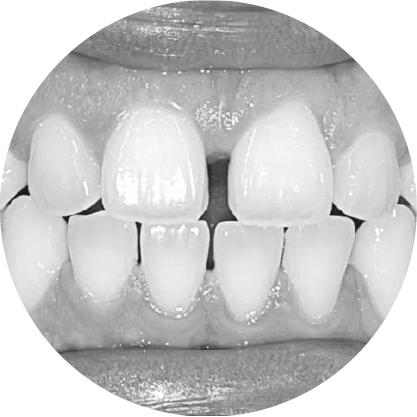

ช่องว่างระหว่างฟัน (Diastema)

การปิดช่องว่างระหว่างฟัน เพื่อรอยยิ้มที่สมบูรณ์แบบ

"ช่องว่างระหว่างฟันหรือไดแอสเทมา หมายถึงช่องว่างระหว่างฟันที่เห็นได้ชัด ซึ่งอาจเป็นปัญหาทางความงามสำหรับหลายๆ คนการจัดฟันสามารถปิดช่องว่าง เหล่านี้ได้อย่างมีประสิทธิภาพทำให้มีรอยยิ้มที่สม่ำเสมอและสวยงาม"

ตัวอย่างในชีวิตจริง